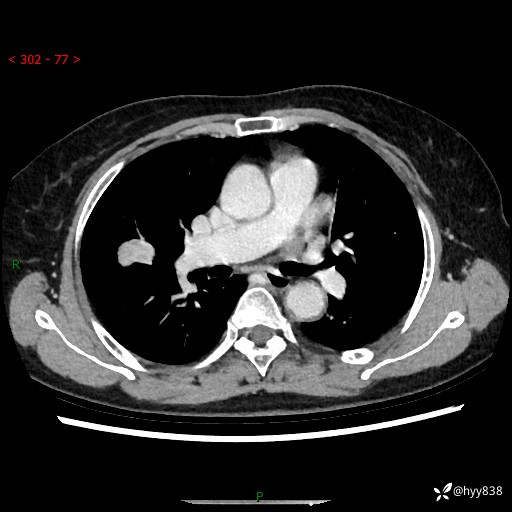

胸部CT平扫+增强